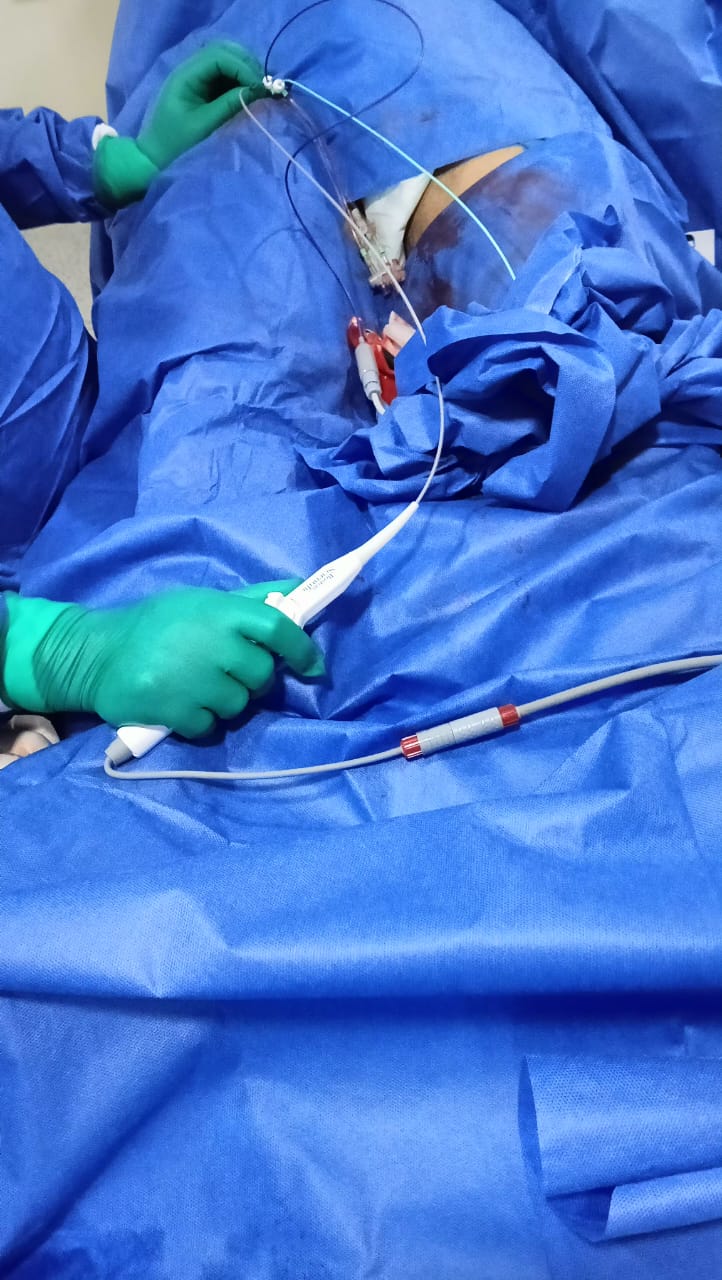

من جانبه أوضح الدكتور حمودة الجزار وكيل وزارة الصحة أنه تم تشغيل جهاز كهربية القلب بمستشفى ميت غمر العام لعلاج اضطراب كهربية وعدم انتظام ضربات القلب بكافة أنواعه من خلال الدراسة الكهروفسيولوجية والكي عن طريق تردد موجات الراديو، وانه يعتبر من أحدث الأجهزة على مستوي العالم تبرعا من المجتمع المدني بقيمة 5.5 مليون جنيه.

وأضاف وكيل وزارة الصحة أنه في أول يوم عمل له في مستشفى ميت غمر استقبلت وحدة القسطرة بالمستشفى مريضا يعاني من خفقان في القلب وتم عمل رسم قلب للمريض وتبين أنه يعاني من تسارع فوق بطيني، وعلى الفور تم دخول الحالة إلى قسطرة القلب وتم عمل قسطرة لدراسة كهروفسيولوجية القلب، وتم خروج المريض بحاله جيده في نفس اليوم.

كما تم في نفس اليوم دخول حالة أخرى لمريض في العقد الخامس من مركز السنبلاوين كان مسجلا بقوائم الانتظار لعمل دراسة كهروفسيولوجية للقلب وتم بالفعل عمل قسطرة قلب وكي البؤرة المسببه لاضطراب ضربات القلب وخرج في نفس اليوم بصحة جيدة.